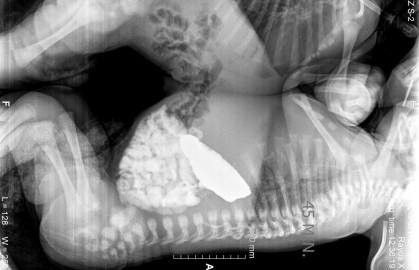

Médicos del Instituto Mexicano del Seguro Social (IMSS), en León, Guanajuato, separaron con éxito a siameses que permanecían unidos por el tórax y abdomen.